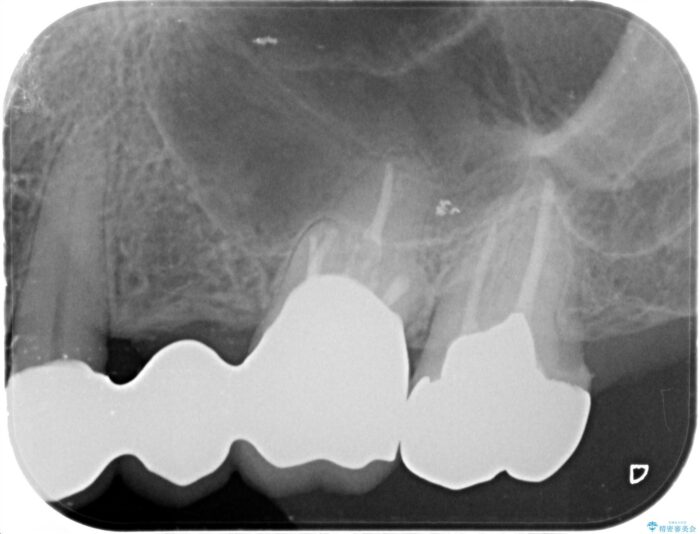

まず検査を行い、歯周病や歯内の問題がないことを確認しました。

銀歯をジルコニアセラミックへと換えることで、審美性・清掃性の高い仕上がりを目指します。